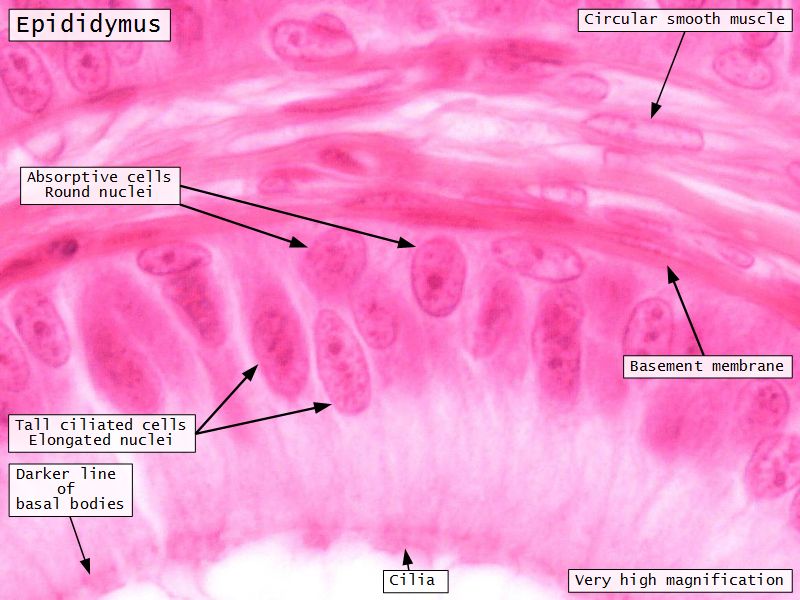

Epididymus

- Simple ciliated columnar epithelium

- Tall ciliated cells

- Elongated nuclei away from BM

- Low absorptive cells

- Spherical nuclei close to BM

- Surrounded circular smooth muscle